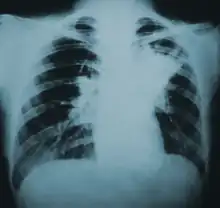

| Lung infiltration in blastomycosis. | |

Blastomycosis manifests as a primary lung infection in about 79% of cases.[8] The onset is relatively slow and symptoms are suggestive of bacterial pneumonia, often leading to initial treatment with antibacterials. Because the symptoms are variable and nonspecific, blastomycosis is often not even considered in differential diagnosis until antibacterial treatment has failed, unless there are known risk factors or skin lesions.[8] The disease may be misdiagnosed as a carcinoma, leading in some cases to surgical removal of the affected tissue.[19] Upper lung lobes are involved somewhat more frequently than lower lobes.[20] If untreated, many cases progress over a period of months to years to become disseminated blastomycosis.

Blastomycosis in the lungs may present a variety of symptoms, or no symptoms at all.[8] If symptoms are present they may range from mild pneumonia resembling a pneumococcal infection to acute respiratory distress syndrome (ARDS).[8] Common symptoms include fever, chills, headache, coughing, difficulty breathing, chest pain, and malaise.[8] Without treatment, cases may progress to chronic pneumonia or ARDS.[8]